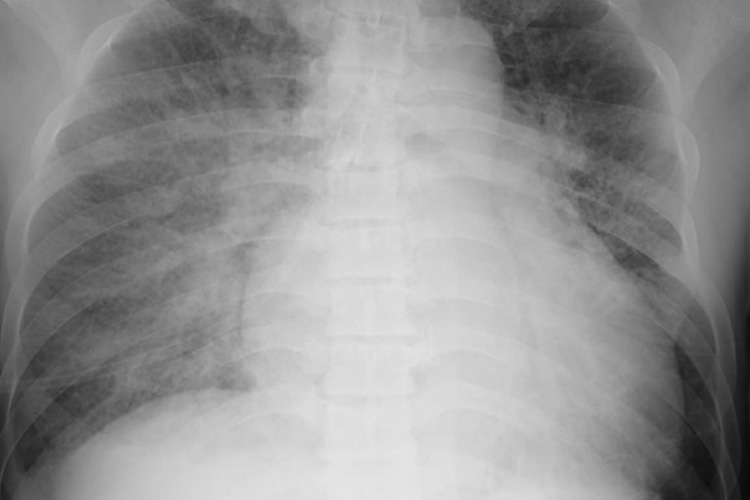

②胸部レントゲン検査

胸部レントゲン検査のイメージ

心不全の存在や重症度診断に重要な検査です。レントゲンでは心臓の拡大、肺うっ血、胸水の有無などを確認します。以前に撮られた画像と比較することも重要です。